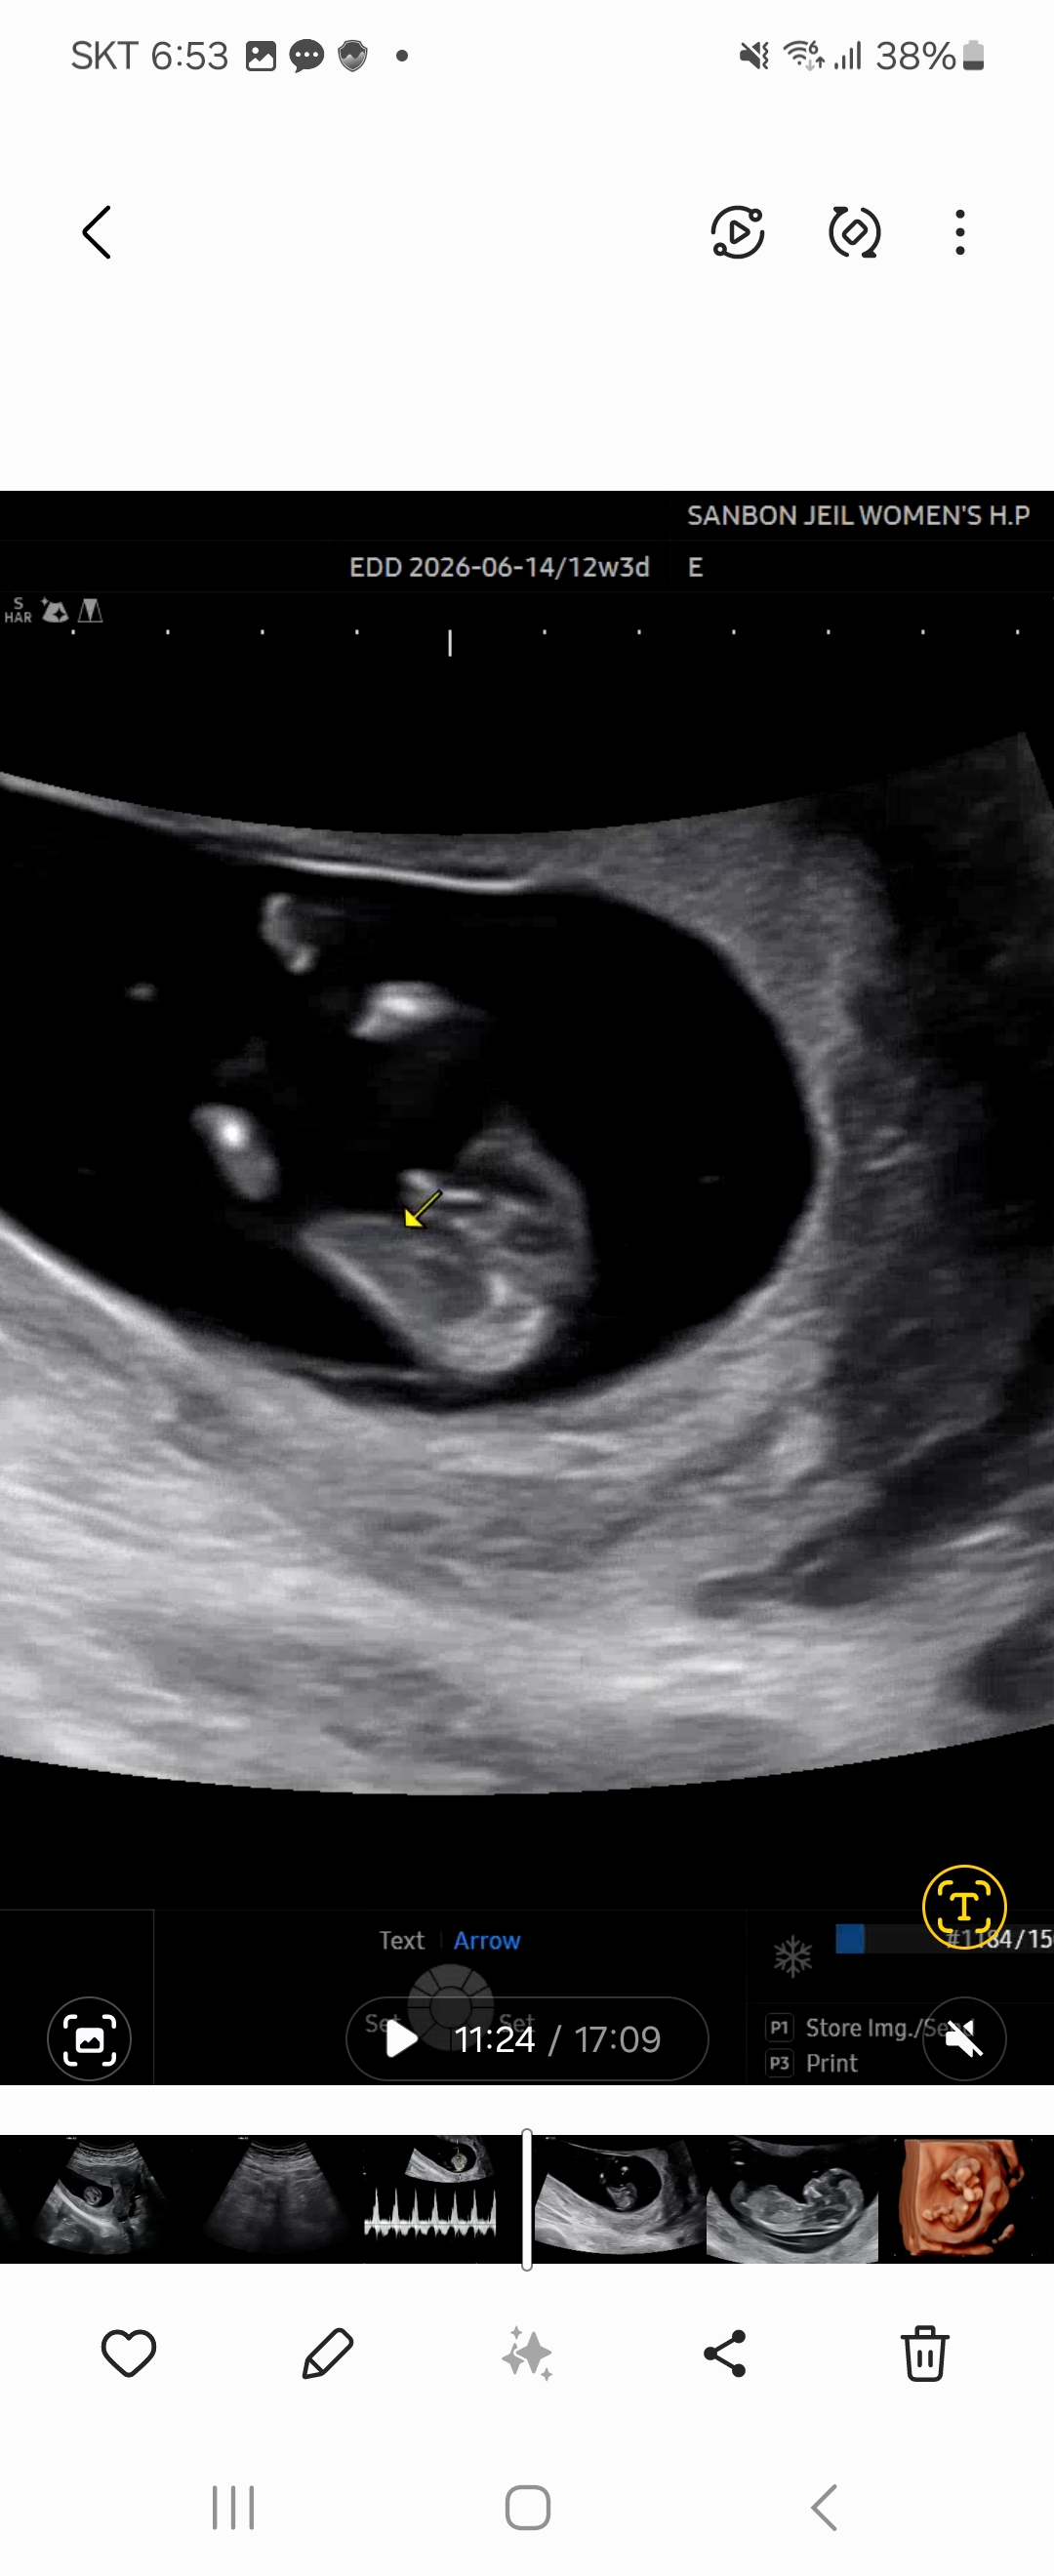

12주 다리사이 봐주길 부탁드립니다~!!

12주 검진때 받은 다리사이 영상 캡처한거에요~ 인터넷을 암만 찾아봐도 비슷한모양이 안보여서 여쭤봅니다 이런모양은 아들에가까울까요 딸에가까울까요?